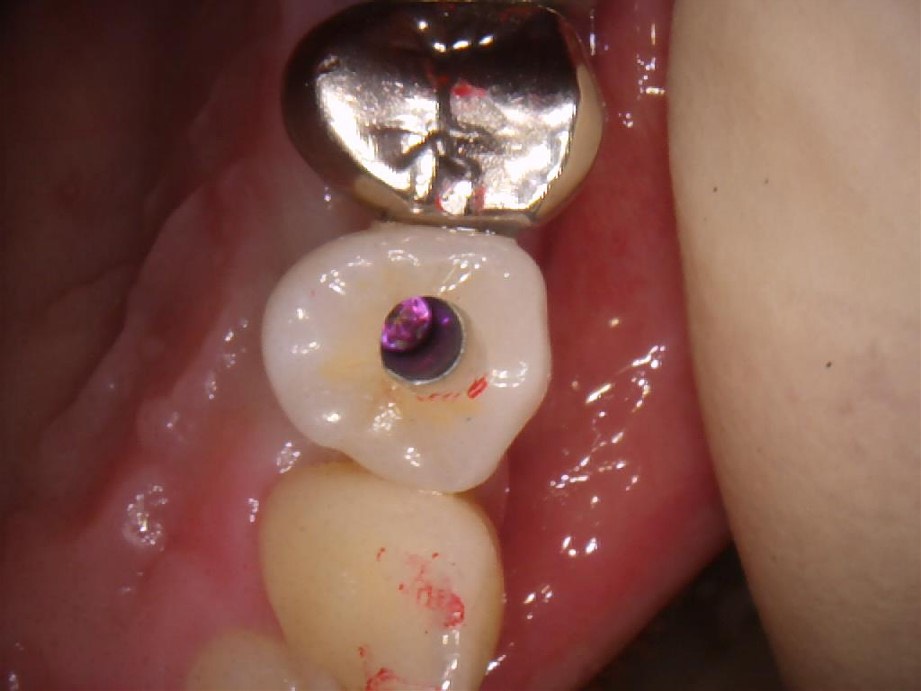

上部構造を装着した写真です。無調整で装着できました。